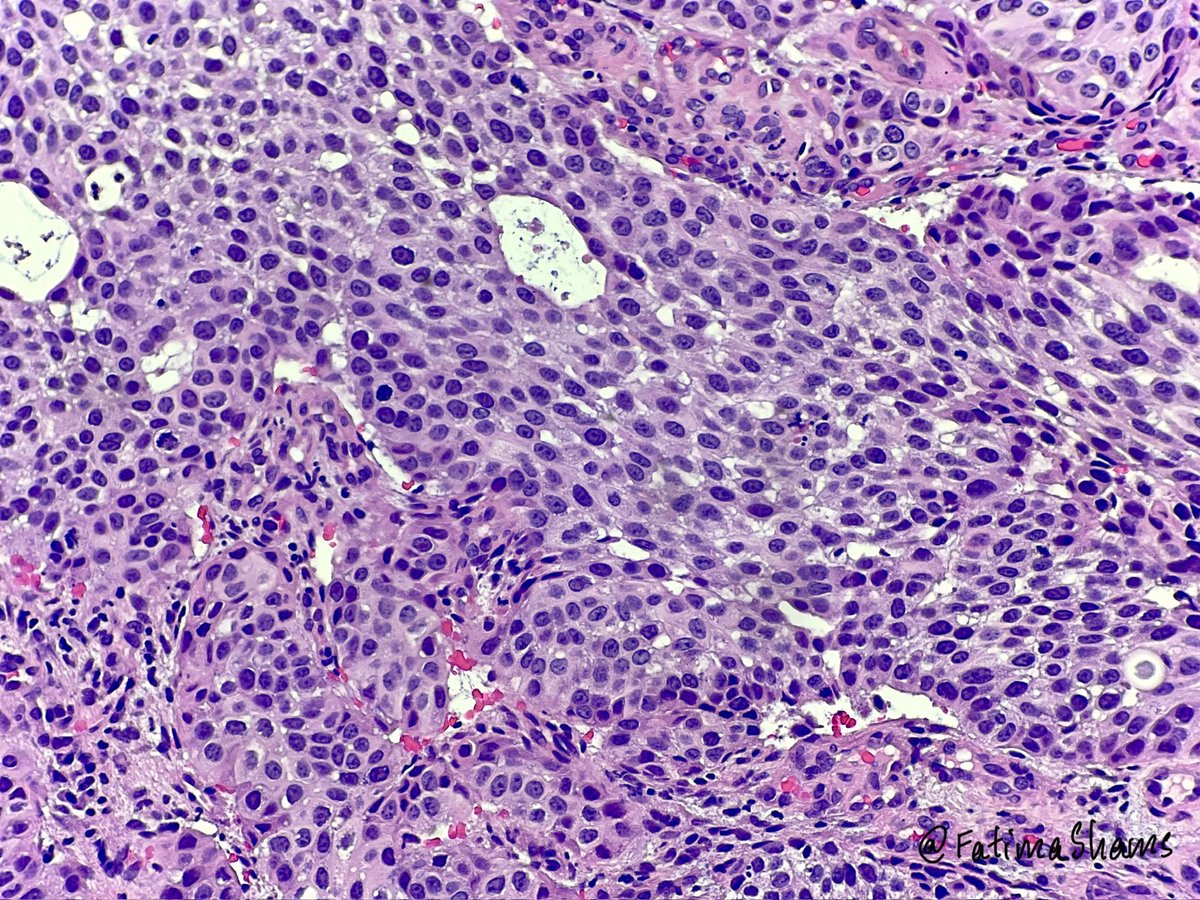

👉68YO female with prior cystectomy for urothelial carcinoma now presents with postmenopausal bleeding and a suspicious cervical mass. ⁉️ What is your diagnosis, and what additional work-up would you perform? #pathtwitter #gynepath #uropath #pathresidents #pathology #surgpath